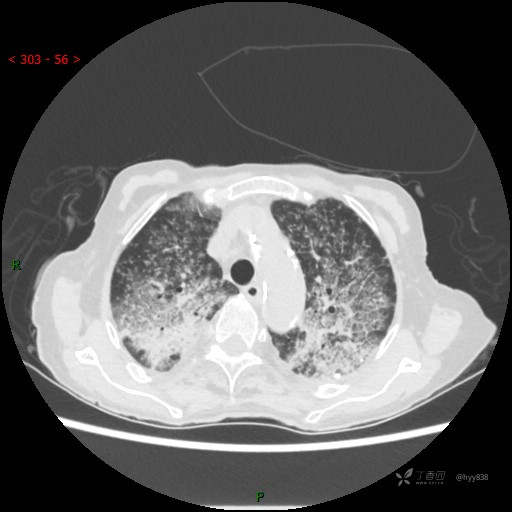

肺部弥漫性、疑难病变,感染或肿瘤?一元论或二元论?贴贴精彩---结果公布~

患者性别:女

患者年龄:73岁

主诉:反复发热10余天

简要病史:患者10余天劳累后出现发热,最高体温达39.5℃,无畏寒、寒战、鼻塞、流涕,无头晕、头痛,无心慌、胸闷、胸痛,无咳嗽、咳痰、气喘,无反酸、烧心、恶心呕吐,无腹痛、腹胀等不适,于2022-5-31至当地中医医院住院治疗,诊断为重症肺炎,予以抗感染、抗病毒等对症支持治疗,仍反复发热,现为求进一步诊治,至我院门诊就诊,门诊以“重症肺炎”收入我科。 起病以来,患者精神、饮食、睡眠差,大小便正常,体力下降,体重无明显变化。

体格检查:T 38℃ P 102次/分 R 17次/分 BP 142/85mmHg,SPO2 84%(未吸氧)。神志清楚,呼吸稍急促,查体合作,咽部充血,未见明显脓点,颈软,全身皮肤黏膜及巩膜未见黄染,浅表淋巴结未触及肿大。双肺呼吸音粗,未闻及明显干湿啰音,HR 102次/分,律齐,各瓣膜区未闻及病理性杂音。腹部平坦,腹软,无压痛,肝脾肋下未触及肿大。双下肢轻度水肿。生理反射存在,病理征阴性。

临床诊断:重症肺炎

胸部CT平扫